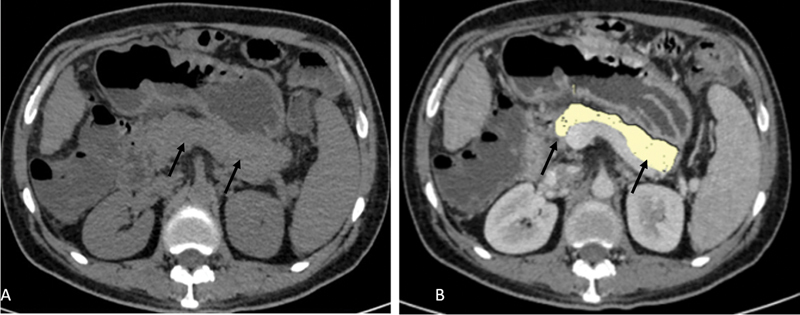

Background  The most crucial step in the management of type 2 diabetes is identifying its pathogenesis and progression. Fat accumulation in the pancreas and decreased parenchymal volume can influence pancreatic function due to insulin resistance or β-cell dysfunction. This study aims to find out the difference in pancreatic volume and fat content by using contrast-enhanced computed tomography (CECT) between normal subjects and patients with different durations of type 2 diabetes mellitus (T2DM). Methods  This was a cross-sectional study. Patients who underwent CECT abdomen for the evaluation of conditions other than pancreatic origin were included. The study group was divided into three subgroups according to the duration of diabetes as <5 years, 5 to 10 years, and >10 years. In total, 40 nondiabetic controls were included. Pancreatic fat volume and parenchymal volume were measured in cm 3 using CECT. Correlation between pancreatic parenchymal and fat volume with the duration of T2DM as well as with levels of hemoglobin A1c, random blood sugar, serum triglyceride, low-density lipoproteins, and high-density lipoproteins was done. Results  T2DM patients had significantly ( p  < 0.001) lower pancreatic parenchymal volume (mean value of 57.08 ± 8.26 cm 3 in diabetics and 72.23 ± 3.41 cm 3 in controls) and higher pancreatic fat volume (mean value of 3.08 ± 1.90 cm 3 in diabetics and 0.67 ± 0.27cm 3 in controls) as compared to nondiabetic controls. In patients with T2DM, as the duration of T2DM increased, pancreatic parenchymal volume decreased and pancreatic fat volume increased. Conclusion  Reduction in pancreatic volume and fat deposition may have a role in the onset and progression of diabetes. Determining the pancreatic volume and fat content would be useful for identifying high-risk patients and determining the pathogenesis of the development of diabetes.

Abstract Image